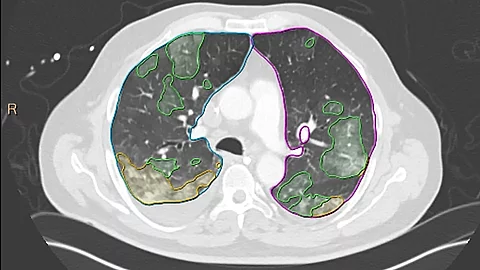

- Pulmologie: CT Pulmo Auto Results ist eine Software zur Entscheidungsunterstützung bei unspezifischen Pneumonien. Die mit komplexen Datensätzen trainierten KI-Algorithmen ermöglichen eine automatische Segmentierung von Läsionen sowie die Klassifikation von Milchglastrübungen und Konsolidierungen im Thorax-CT. Die automatisch erstellten Berichte enthalten Ergebnisse der Volumen-Messung und Daten zur Verteilung der Läsionen. Das erleichtert, insbesondere bei COVID-19-Verdacht, die quantitative Beurteilung von Lungeninfiltraten und erhöht die diagnostische Sicherheit – bei gleichbleibender Befundungsdauer.